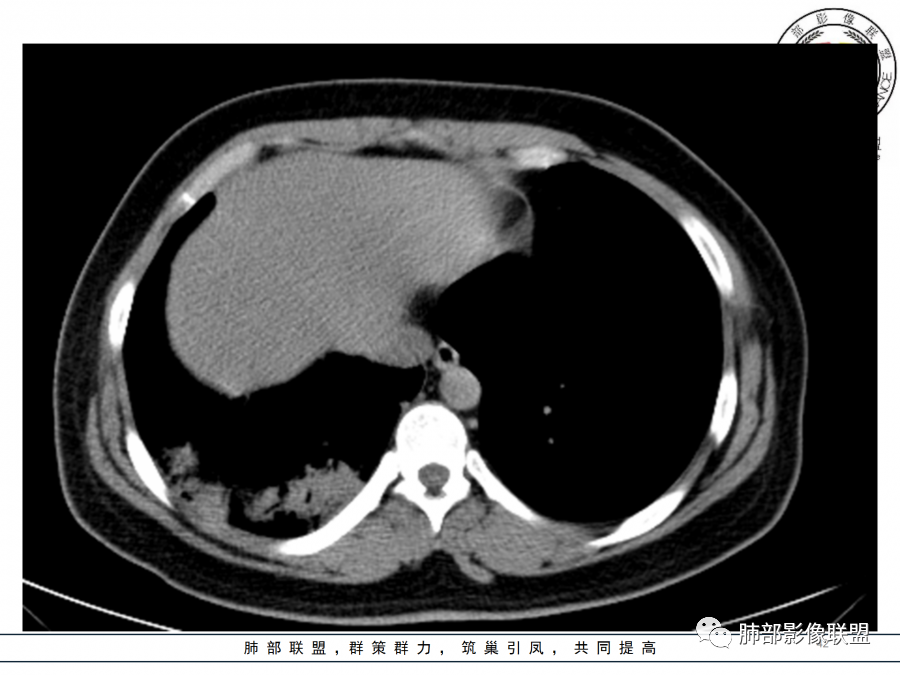

1.年轻女性,咳嗽、发热(38.8°),起病急,血象高。影像上大片实变影为主,一般会首先考虑细菌性肺炎,尤其是肺炎链球菌感染等。疗效不满意时考虑其他。

2.影像上怀疑其他病灶的理由有:

1)实变影为大小不等多中心性。

2)沿胸膜下分布趋势(不同于大叶性肺炎的肺叶“造型”)。

3)周围较大范围磨玻璃影及小叶间隔增厚。

4)病灶体积增大明显(叶间裂推移)。

3.腺病毒肺炎可以符合上述改变:实性密度,间质分布为主等。

4.隐球菌感染可以符合上述改变:胸膜下多中心实变密度为主,磨玻璃晕等。但隐球菌临床症状大多隐匿、迁延,影像变化缓慢。

5.本例患者血象高,影像渗出明显,尚不能排除混合感染可能。